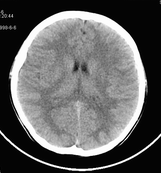

男,10岁,因近来常头痛就诊。先平扫拟诊右侧脉络膜裂囊肿,后薄层(3mm)扫描见此灶与右侧脑室后角相通,且向内几乎与鞍上池相连,并见一血管影沿其走形 (可能是脉络膜前动脉)。1。请教:脉络膜裂或脉络膜裂囊肿与侧脑室颞角或鞍上池相通吗?好像谁说脉络膜裂是脉络膜从外侧裂向侧脑室移行的裂隙。请高手讲讲这点的解剖关系。2。建议:对于老年患者,有丘脑附近特别是右丘脑附近的近似腔隙性梗死灶,临床症状不明显的,应做3mm薄层扫描,看病灶向下是否与侧脑室颞角相连,以免误诊。